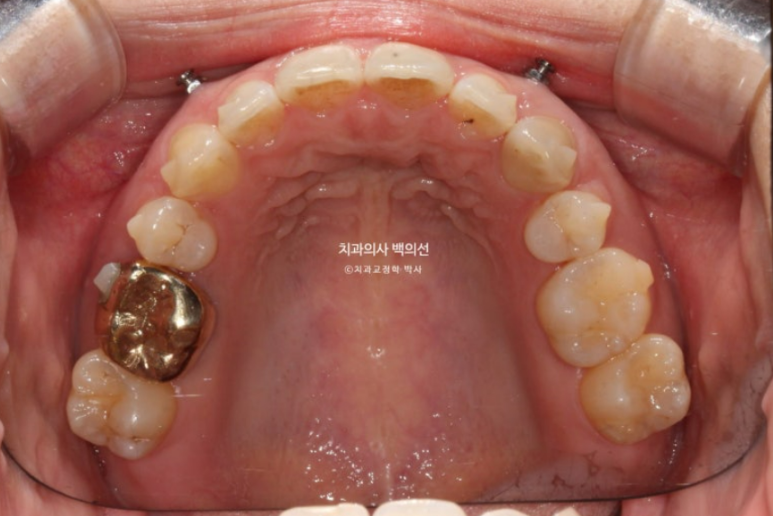

작년 3월 과개교합과 발치공간 벌어짐 때문에 재교정을 위해 찾아온 30대 환자분입니다.

아랫니가 안 보일 정도로 과개교합이 심합니다.

24.03

과개교합이 심하면 위 앞니 뒤에 철사유지장치를 붙일 수 없습니다. 아랫니에 씹혀 불편하고 또 철사가 금방 떨어집니다.

송곳니 뒤쪽 2mm정도의 벌어진 공간이 보입니다.

10년 전 외국에서 교정할 때 발치한 첫번째 작은어금니가 있었던 공간이고, 재발로 인해 공간이 다시 벌어졌습니다.

이분처럼 과개교합이 남은채로 교정이 마무리 되면 철사유지장치를 붙일 수 없으며 이는 곧 재발로 이어집니다. 철사유지장치가 잘 붙어있었다면 발치공간이 2mm씩이나 벌어지진 않았을 것 입니다. 교정 마무리 단계에서 과개교합만큼은 반드시 끝장을 봐야 하는 이유입니다.